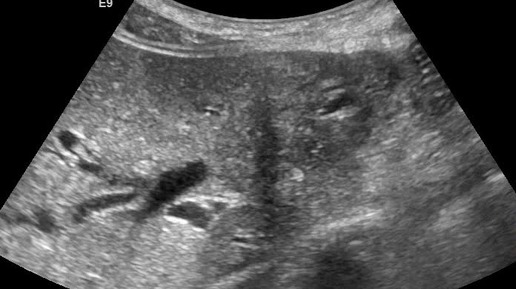

Ультразвуковые находки от врача УЗД Зорина Я.П.